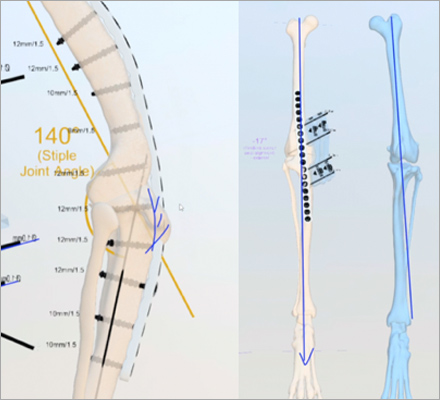

V-pop 프로그램을 이용한

세심한 수술 계획,

수술 중 발생할 수 있는 변수 조절

예은동물의료센터는 V-pop 프로그램을 이용하여 세심한 수술 계획을 세우고 수술 중 발생할 수 있는 변수 조절합니다.

또한 다양한 정형외과 회사 제품 보유로 환자 맞춤 수술 가능합니다.

다양한 크기/다양한 뼈 모양에 가능한 기구 보유하여 리허설을 통해서 환자에게 가장 적합한 플레이트 이용합니다.